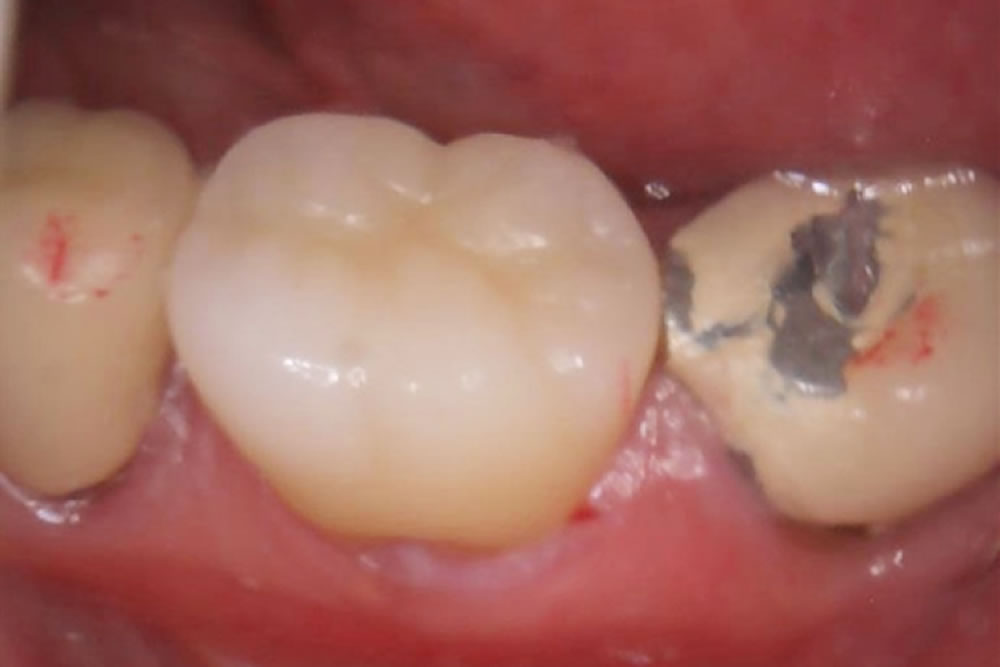

ジルコニアクラウンをセット・治療完了

歯と歯の間隔や噛み合わせを調整してから専用のセメントで接着していきます。

ジルコニアクラウンは硬いため、場合によっては実際に食事などを行ってもらった後、再度嚙み合わせの調整を行います。